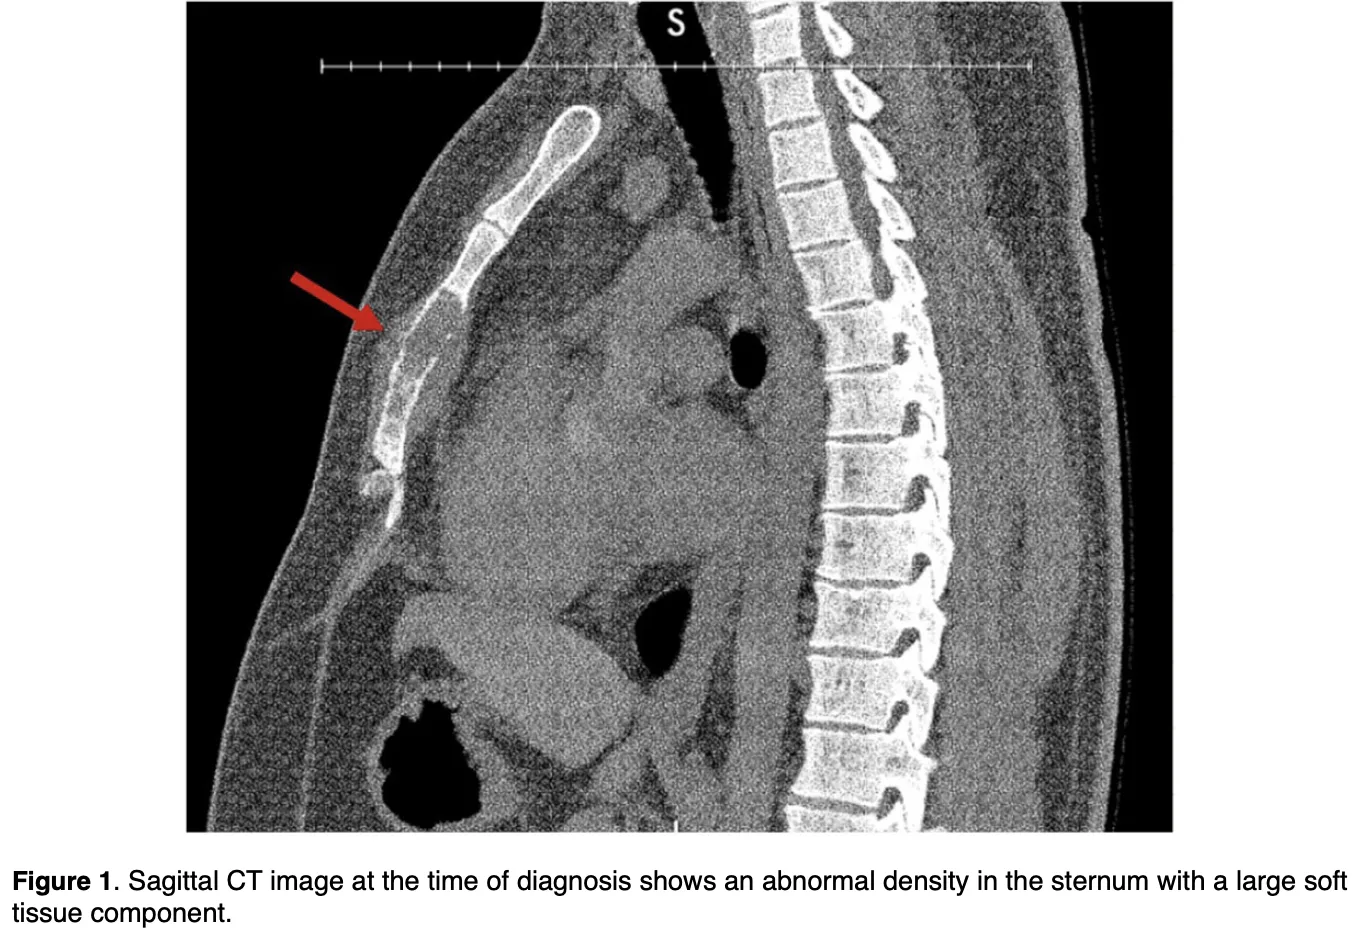

胸骨腫瘍の画像診断

骨が破壊され, 骨の外に腫瘍が拡がっています.

胸骨腫瘍の患者さんの画像ができあがったので, 確認.

CTでは, 骨が破壊されて, 骨強度が低下した結果, 骨折を合併していました.

骨強度が低下したことによる骨折を, 病的骨折といいます.

また, 骨内の病変が骨の外に出ている所見も認められました.

骨の中の病変が骨を壊して外に出る場合, 悪性の骨腫瘍を強く疑う必要があります.

MRIの結果, 骨内の病変や骨の外の病変は, 造影剤で白く染まっており, 細菌感染より腫瘍が強く疑われました.